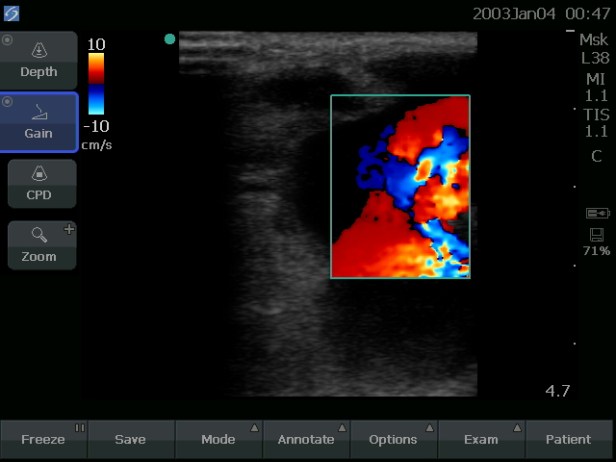

Upon placing the ultrasound probe on the patient’s forearm, he immediately realized this was not an abscess; the fluid collection didn’t look right. When color flow was placed on the large, round fluid collection, the fluid was pulsing! This was, in fact, either a pseudoaneurysm or aneurysm of the radial artery with a fistula between the cephalic vein and radial artery. In essence, the knife wound in January had poked a hole in the artery in the patient’s upper forearm and connected the artery to the nearby vein. Every time the artery pulsed, it had been pushing blood into the vein and the surrounding soft tissue. These ultrasound findings were reinforced by the fact that the patient had only a very faint pulse at his wrist near his right thumb (the distal radial artery), but a very strong pulse in his left wrist. If Alfunsi had cut open this wound, it would have bled all over the room, and the patient could even have lost his arm. Instead of antibiotics or cutting open the swelling with a scalpel, this patient needed a vascular surgeon to repair the artery and vein.